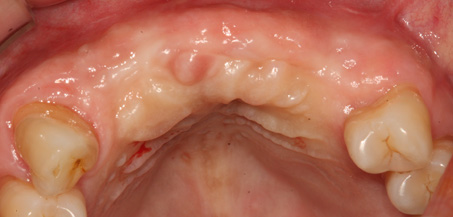

B

A